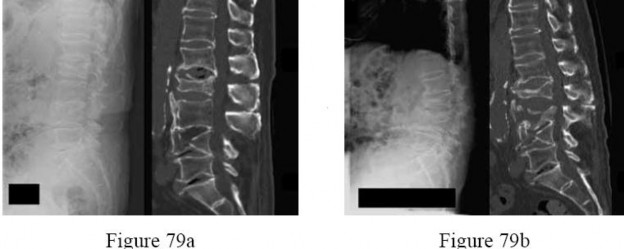

A 67-year-old man who underwent total hip arthroplasty (THA) 4 years ago fell on to his right hip. His pre-injury right hip film is seen in Figure A while films of his current injury are seen in Figures B and C. Prior to the fall he had no thigh or hip pain. His ESR and CRP are within normal limits. During intraoperative assessment, the acetabular and femoral stems are found to be well fixed. What is the next best course of action?

This patient has a periprosthetic hip fracture at the level of the stem with a stable prosthesis, indicated open reduction and internal fixation as the treatment of choice.

The Vancouver Classification can be helpful in clinical decision-making regarding fixation versus revision of periprosthetic hip fractures of the proximal femur. A stable implant, by nature, does not need to be revised in the setting of adequate bone stock for fixation, but the ultimate test of stability should be in the operating room. Many fixation strategies are appropriate, but many implants include locking plate fixation for concerns of stress-shielded bone around the implant as well as use of unicortical fixation at the level of the stem.

Pike et al review the current trends in treating B1 fractures including locking plates with strut allografts, minimally invasive plate osteosynthesis (MIPO) and locking plates spanning femoral THA and TKA stems in selected patients. The authors conclude that no studies currently provide evidence establishing one

technique over the other and recommend treatment on a case by case basis.

Illustration A shows a possible fixation construct for this patient's fracture. The Vancouver Classification is seen in Illustration B and Illustration C represents an algorithm for treatment options.